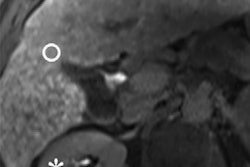

Due to heightened interest in researching chronic liver diseases, Resoundant has grown its services to core labs for clinical trials to meet growing demand. Working together, Resoundant and Mayo Clinic will use MR elastography and imaging of proton density fat fraction, which were pioneered by Resoundant, to move clinical trials forward.

These noninvasive technologies are used in trials as key biomarkers due to their rapid acquisition protocols, superior accuracy, repeatability, and wide availability, according to the company.